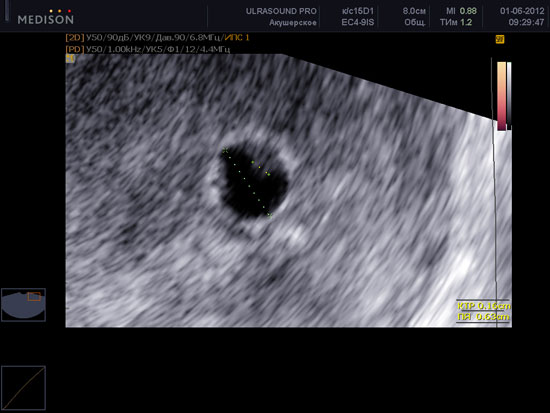

Узи в 4 недели беременности - это, как правило, первое ультразвуковое исследование

УЗИ в 4 недели беременности — что покажет и для чего его делать?

УЗИ в 4 недели беременности делают обычно для того, чтобы подтвердить её факт. Также специалист оценивает процесс беременности и расположение яйца. Как правило, к...